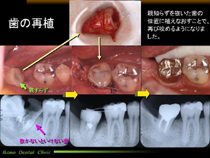

歯の再植手術

歯の再植手術とは、抜歯しないといけない時に、親知らずなど機能していない歯を抜いて、抜歯した歯の部分に移植してあげることで活用する方法です。

歯根膜という自分の歯の組織を利用して歯と骨を結合させる方法です。

歯の再植

当院での治療例(クリックで拡大)

親知らずの手前の歯が保存不能になりましたので、 その歯を抜歯した場所に奥の親知らずを移植しました